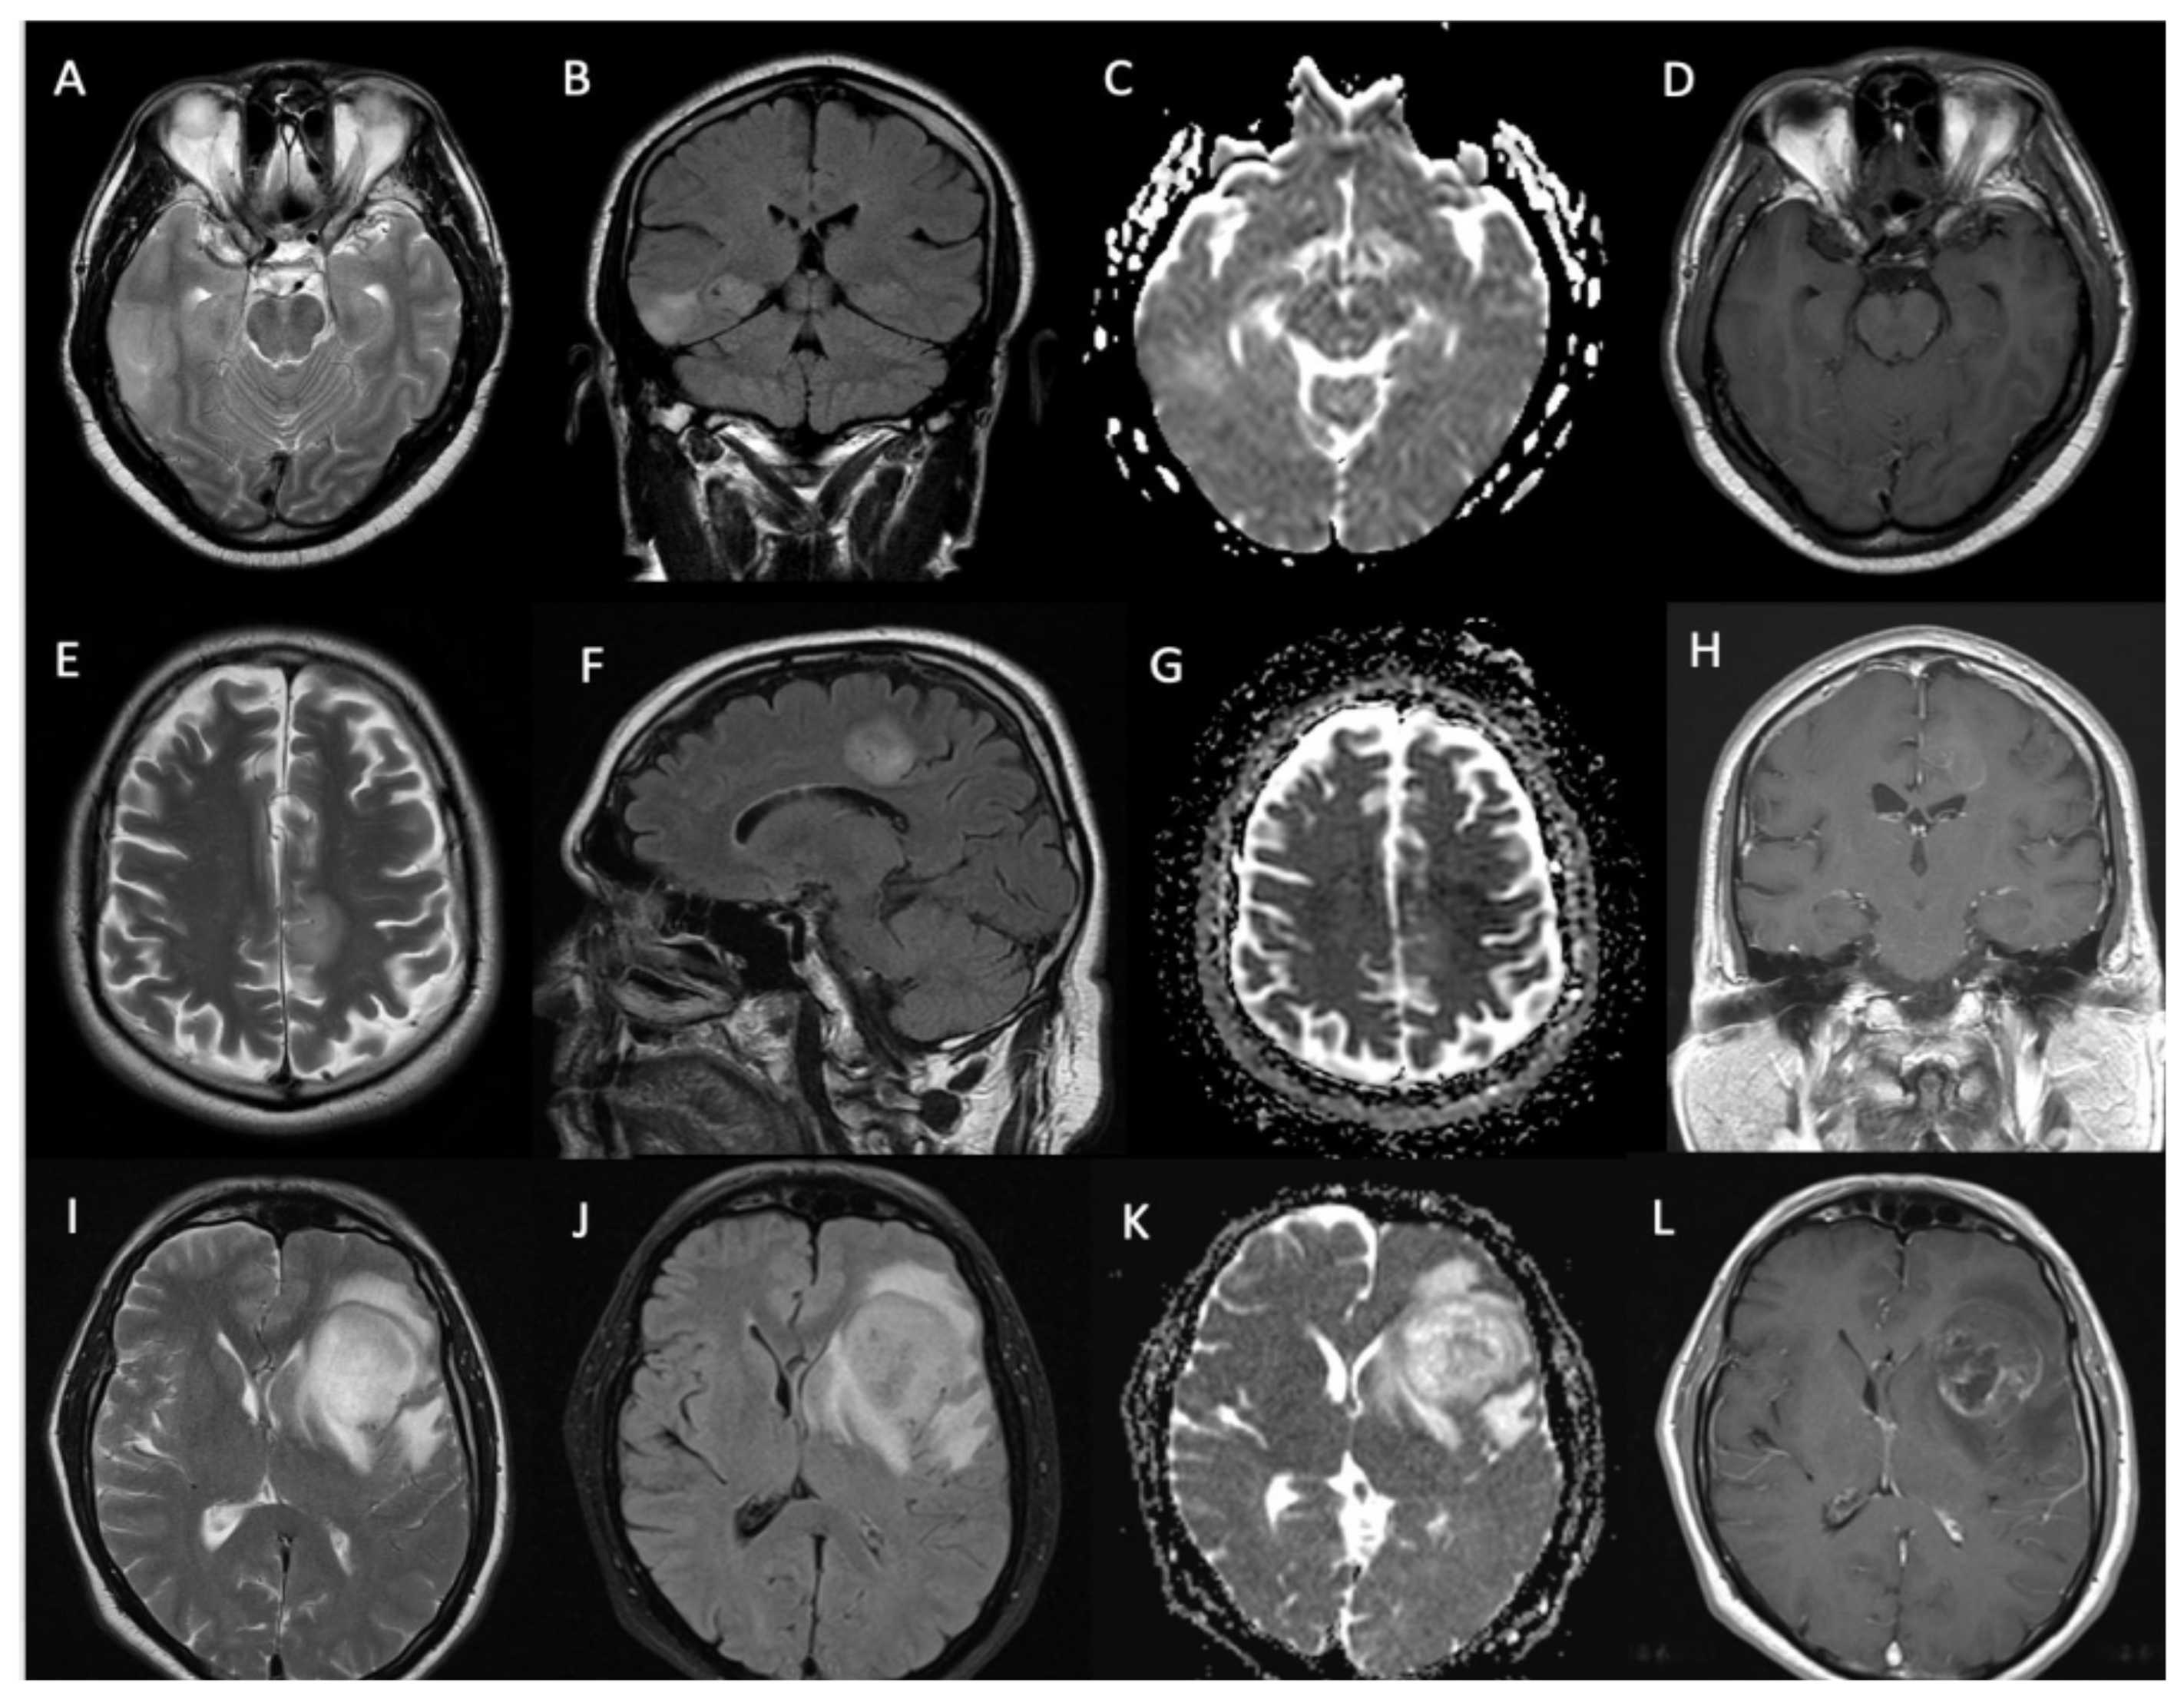

3.3. Imaging Characteristics

| Radiological characteristics | Numbers (percentage) |

| Location (n = 54) | |

| Lobar | 46 (85%) |

| Deep-seated | 8 (15%) |

| Contrast enhancement | |

| Solid pattern | 18 (33%) |

| Rim enhancement | 17 (31%) |

| Non-enhancing | 19 (36%) |